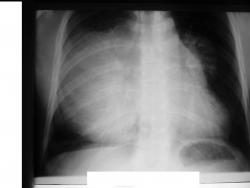

Мужчина 36 лет, рентгеногафия и КТ грудной полости.

Жалобы на субфебрильную температуру, боли в грудной клетке справа, слабость, похудание. ФГ 10 месяцев назад - норма.

Снимки от 18.08.09

Снимки 28.08.09

Интенсивное, однородное затемнение в средних отделах справа, слева норма - мною был заподозрен м/долевой плеврит, пациент был направлен в областной центр торакальной хирургии. Затем онкодиспансер, затем институт рака в Киеве. Результат гистологии тератобластома средостения. 2 курса химиотерапии контрольное КТ в октябре - отрицательная динамика.

Массивное неоднородное мягкотканное новообразование, исходящее из верхней или средней трети переднего средостения, оттесняет крупные сосуды вправо и кзади. По локализации должна быть злокачественная тимома. Хотя и лимфому наверное, не стоит отбрасывать, Ходжкинская маловероятна.